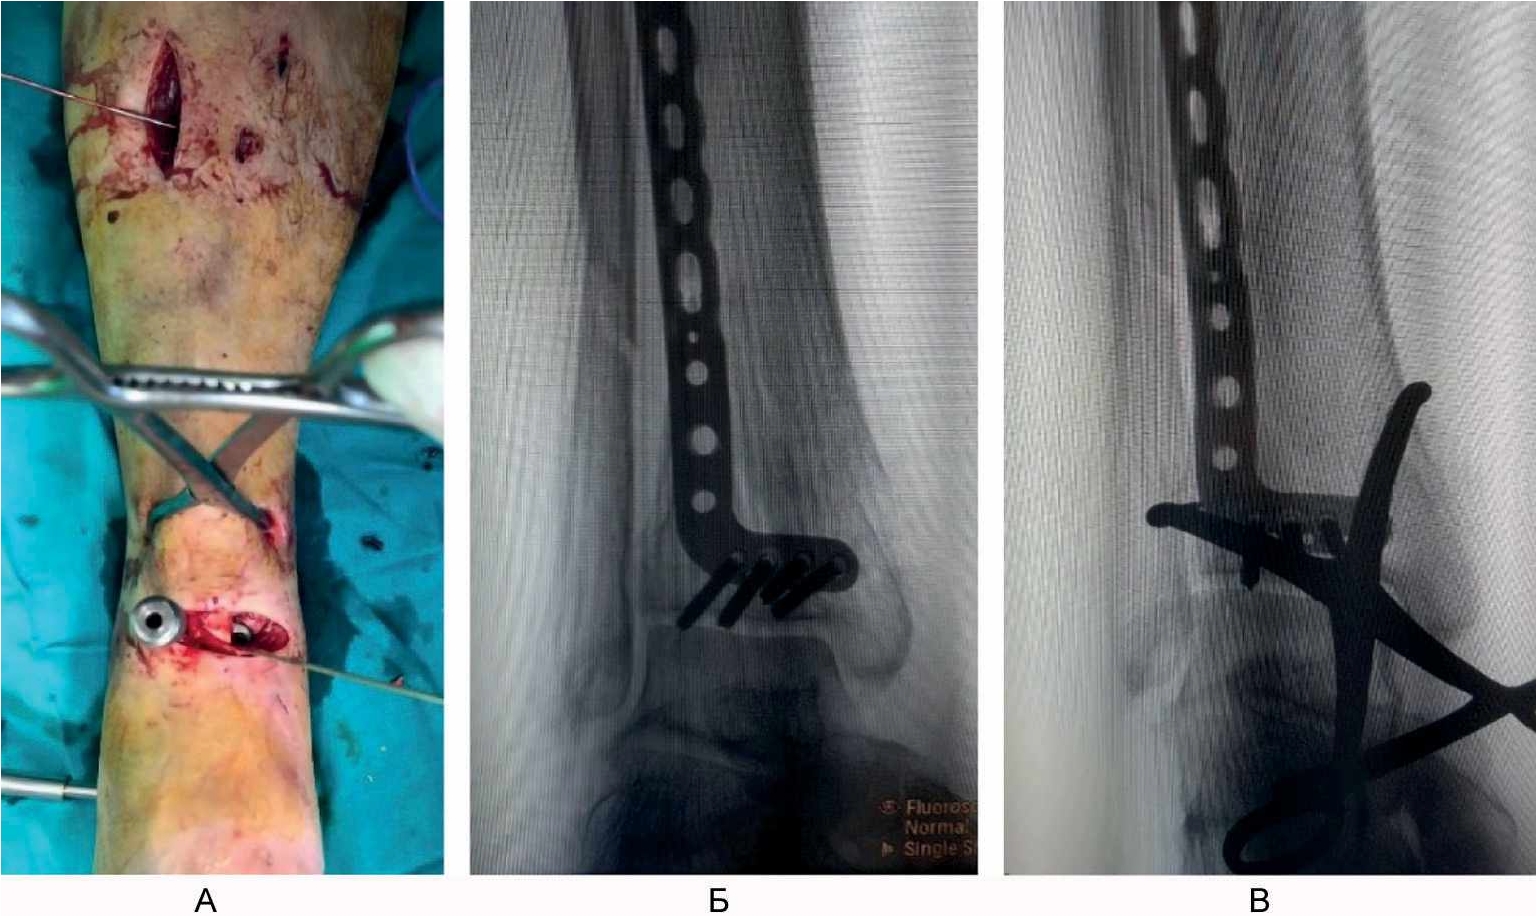

Выполнили поперечный разрез кожи и поверхностной фасции на передней поверхности голени на 1–2 см выше проекции щели голеностопного сустава. Путем продольной тупой диссекции сформировали 2 окна для доступа к большеберцовой кости между проксимальной и дистальной порциями удерживателя сухожилий разгибателей: 1-е – между длинным разгибателем I пальца стопы и длинным разгибателем пальцев стопы, 2-е – латеральнее длинного разгибателя пальцев стопы. Через сформированные окна снизу вверх эпипериостально ввели анатомически предызогнутую пластину для дистального отдела большеберцовой кости до тех пор, пока дистальный ее конец не достиг уровня субхондрального слоя большеберцовой кости. Затем пластина была предварительно фиксирована к кости спицей Киршнера. Окончательную репозицию перелома в метафизарной зоне выполнили чрескожно с использованием остроконечных репозиционных щипцов. На уровне проксимального конца пластины на переднелатеральной поверхности голени осуществили проксимальный разрез кожи и мягких тканей длиной 3 см, минимально необходимый для визуализации пластины. Пластину фиксировали к кости винтами с угловой стабильностью, введя через дистальный и проксимальный доступы ниже и выше зоны перелома, соответственно, по 4 винта. Обнажение зоны метафиза и области перелома не выполняли, что сохранило перифрактурную гематому и создало оптимальные условия для сращения перелома (рис. 4).

Рис. 4. Малоинвазивный остеосинтез минимизирует ятрогенную травму мягких тканей и нарушение кровоснабжения отломков кости. А – закрытая репозиция остроконечными репозиционными щипцами; Б, В – интраоперационные рентгенограммы при установке опорной пластины.